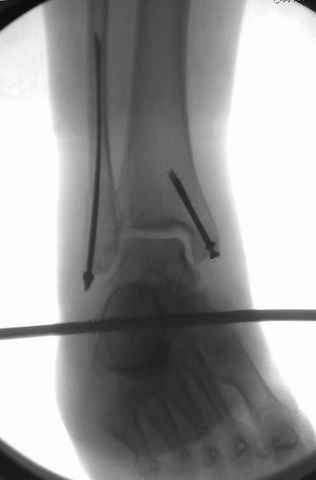

На снимках варианты фиксации малоберцовой:

№ 1 двух лодыжек